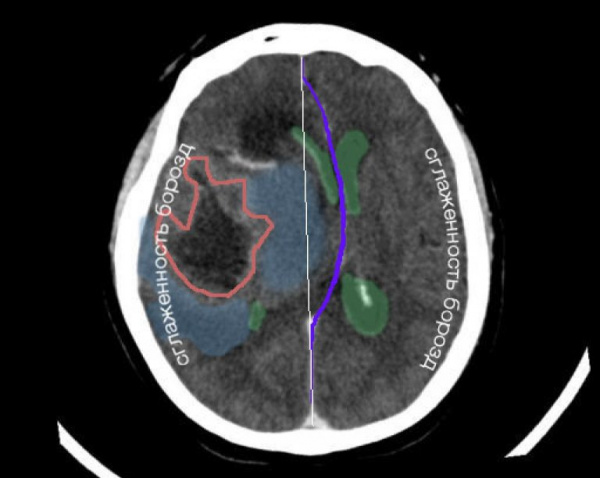

• Выраженный отек-набухание головного мозга

• Компрессия и прижатие извилин о свод черепа

• Сглаженность борозд